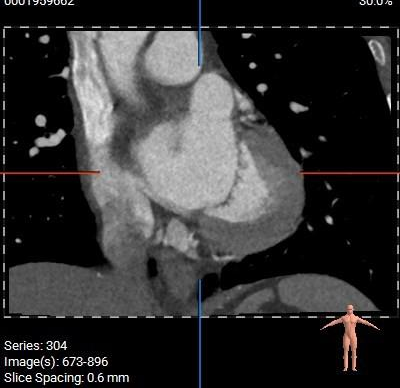

CT分析

主动脉根部:

主动脉根部径线:

Annulus23.7mm

LVOT23.6mm

L28.4*R27.4*N28.8

SOVP89.9mm

STJ26.6mm

AA31.9mm

LV39.8mm

LV40.6mm

多平面分析:

Sub-223.8mm

Super-223.7mm

Super-425.2mm

Super-624.3mm

Super-825.4mm

Super-1025.4mm

双侧冠脉开口高度可,左侧瓣叶略长,预估左侧冠脉遮挡风险较低:

中度高位钙化,钙化分布较均匀,瓣膜锚定力可,形态影响较小:

左心耳及心室未见血栓,瓣环水平夹角57°,近横位心: